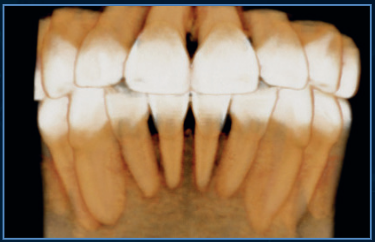

Our flagship high resolution tomograph delivers cutting-edge image quality that allows you to visualize anatomy and pathology beyond traditional CBCT standards. This comes from its unique flat panel detector (FPD), which provides an industry-smallest, 0.2mm focal spot. Investing in the Excelsior ENDO mean offering patients superior diagnostics and setting a practice apart as a leader in dental imaging.

The powerful system components of the PreXion Excelsior Endo enable an extraordinary combination of the most precise 3D imaging, large image detail, lowest radiation exposure, reliable diagnostics and digital planning, which is optimized specifically for endodontic diagnostics and treatment with its flat panel detector (FPD) providing an industry-leading 02.mm focal spot. Its patient management system is designed for secure and networked communication of patient data across multiple rooms within a practice and can be integrated into the existing infrastructure with ease.